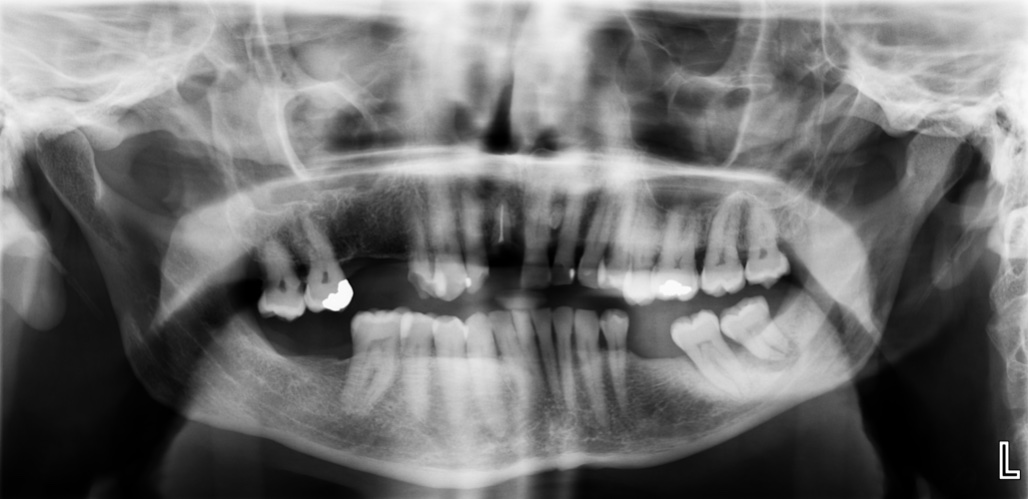

Question: S14 PM 27.7 Using the print of radiograph BMC40, answer the following question on the answer score sheet. (Select ONE OR MORE correct answers.) Which of the following is/are evident on the print of the radiograph?